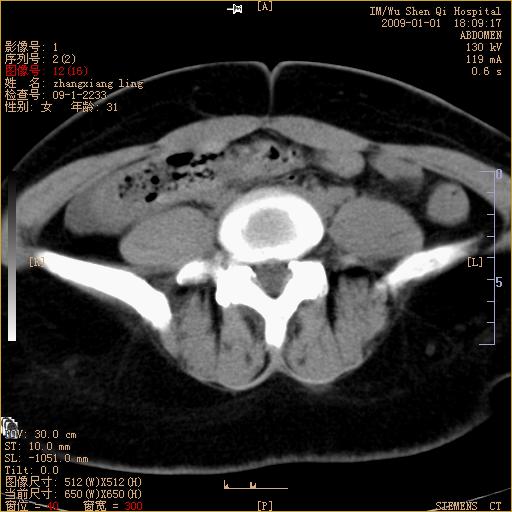

标题: CT17527:F31Y,腹痛伴血便9小时 [打印本页]

标题: CT17527:F31Y,腹痛伴血便9小时

升结肠肠壁不规则增厚,肠腔狭窄,考虑升结肠占位,建议增强扫描

升结肠肠壁不规则增厚,肠腔狭窄,考虑升结肠占位,建议增强扫描,不除外肠套叠.

升结肠肠壁不规则增厚,似呈同心圆改变,其有积液。结合病史首先考虑肠套叠伴肠壁坏死可能性大,结肠肿瘤待排。

患者已手术,结果肠系膜血栓形成肠坏死

结果:患者已手术,结果肠系膜血栓形成肠坏死。回过头再看局部肠壁增厚有分层(高密度坏死及低密度水肿)表现。